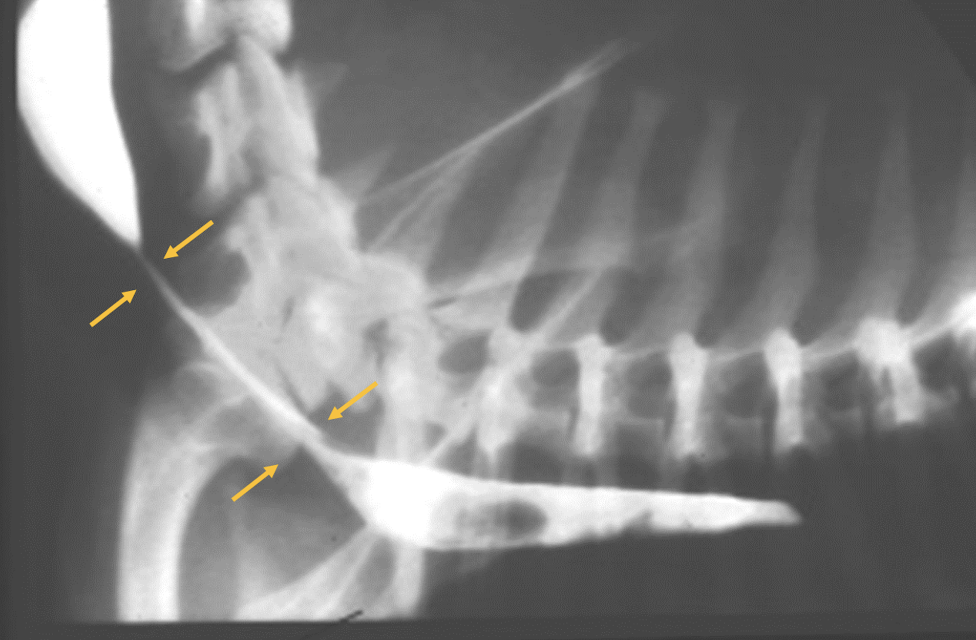

Persistent right aortic arch

What is a key finding for persistent right aortic arch?

Focal leftward deviation of the trachea